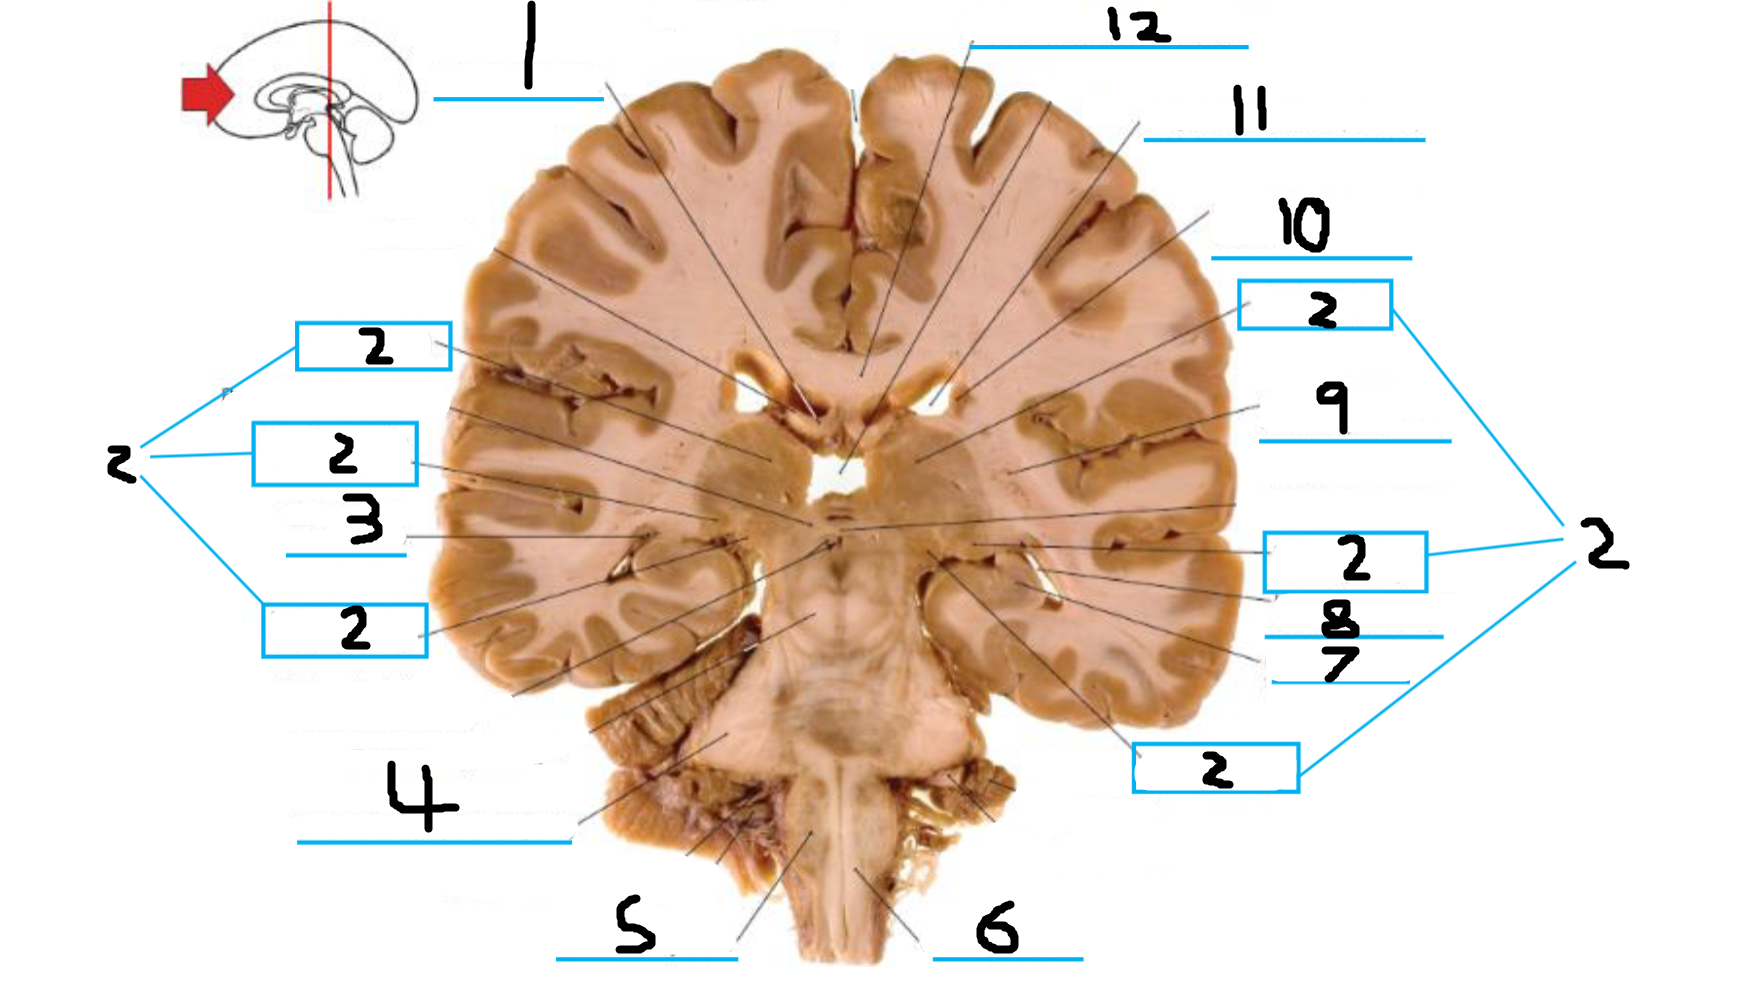

#1 is the:

Cingulate Gyrus

#2 is the:

Septum Pellucidum

#3 is the:

Lateral Ventricle

#4, #7, and #12 is the:

Fornix

#5 is the:

Third Ventricle

#6 is the:

Anterior Commissure

#8 and #11 is the:

Amygdala

#9 is the:

Hypothalamus

#10 is the:

Mammillary Body

#13 is the:

Insula

#14 is the:

Globus Pallidus

#15 is the:

Putamen

#16 is the:

Internal Capsule

#17 is the:

Caudate

#18 is the:

Corpus Callosum

#3 and #16 are the:

Thalamus

#4 is the:

#5 and #9 is the:

Hippocampus

Crus Cerebri

#7 is the:

Basilar Pons

#8 is the: